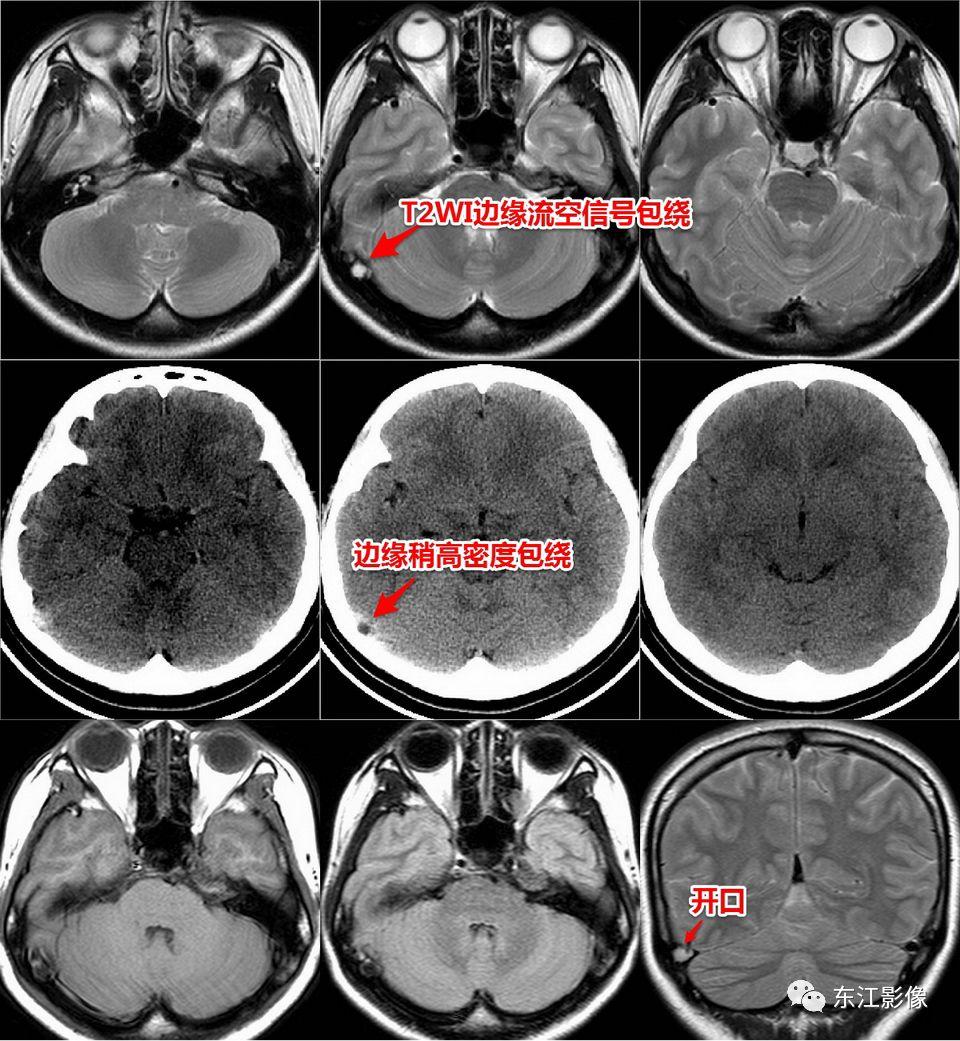

2. 静脉窦内扩大的蛛网膜颗粒

- 蛛网膜在硬脑膜构成的静脉窦附近形成许多绒毛状突起,突入静脉窦内,形成静脉窦内蛛网膜颗粒。

- 随着头颅MRI的广泛使用,静脉窦内扩大的蛛网膜颗粒“变得”非常常见。

- 不熟悉的话,容易误诊为异常。

- 以横窦常见(横断面图像最容易被发现的缘故),其次为上矢状窦,直窦、乙状窦少见,海绵窦罕见。

- CT平扫,呈稍高密度背景内低密度充盈缺损。

- MRI T1WI为低信号,稍高于脑脊液信号;T2WI为高信号,FLAIR多为低信号,稍高于脑脊液信号,较大的其内可见絮状稍高信号;增强多无强化,较大的其内可见点、线状强化灶。MRV上均呈附壁状充盈缺损。

- 极少数静脉窦内扩大的蛛网膜颗粒可能会引起静脉窦狭窄,DSA实时压力测量是确诊工具。

右侧横窦扩大的蛛网膜颗粒。

左侧横窦扩大的蛛网膜颗粒。

上矢状窦、直窦多发扩大的蛛网膜颗粒,薄层T2WI切线面显示更佳。